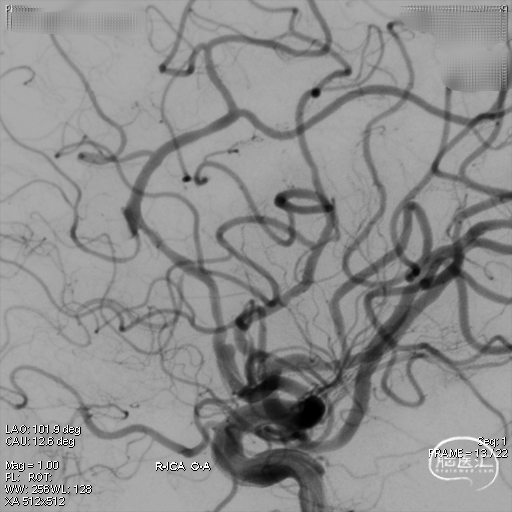

DSA:提示左侧大脑前动脉A2段动脉瘤,其他血管造影未见明显异常。

术后造影:支架覆盖夹层动脉瘤,贴壁良好。

术后造影:

强易达(Choydar)血流导向密网支架术中操作顺利,支架推送及释放过程平顺,未见管壁损伤,支架喇叭口形状设计贴壁效果好;径向支撑力高。